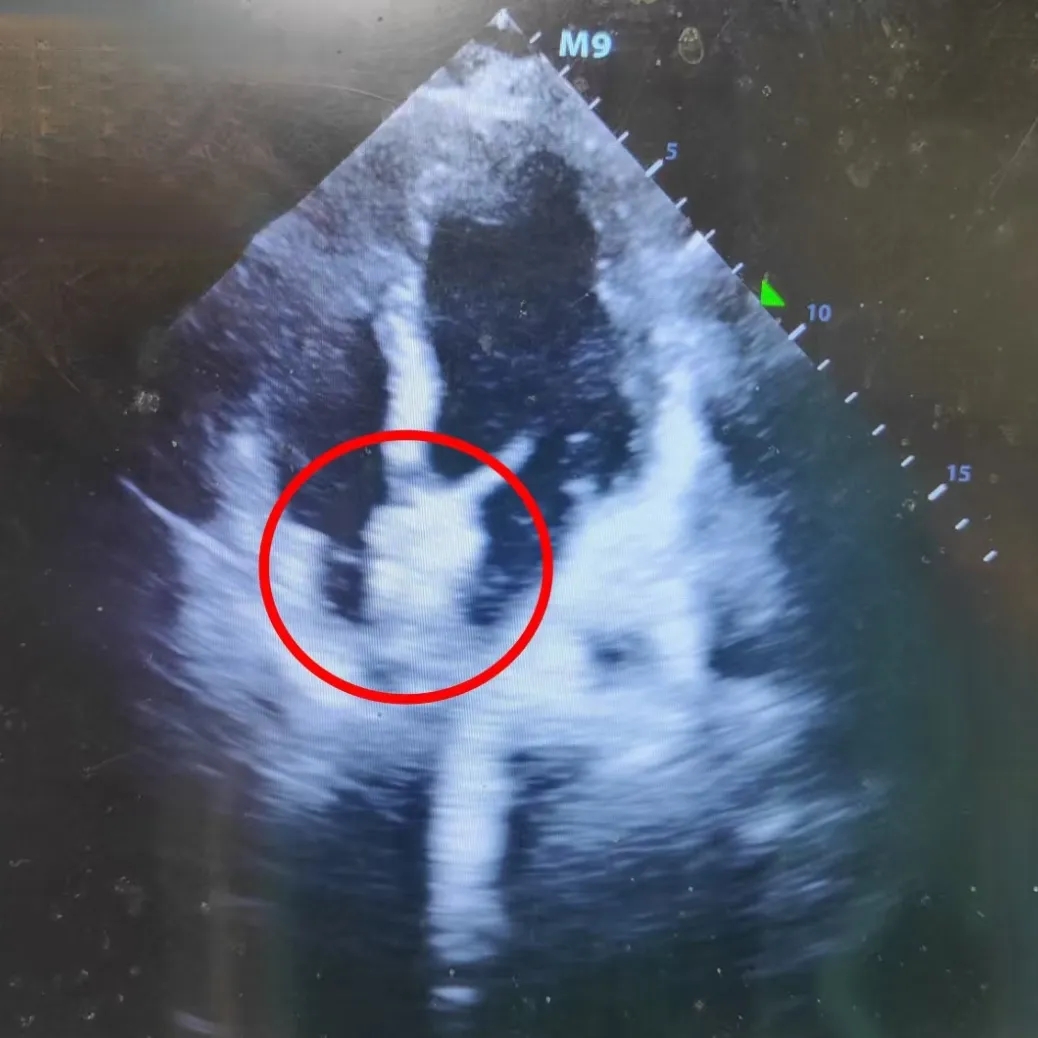

四腔心切面

双房心切面

超声下可见封堵器盘面平整,位置固定,稳固夹持缺损

超声四腔心切面可见封堵器盘面贴合,形态良好